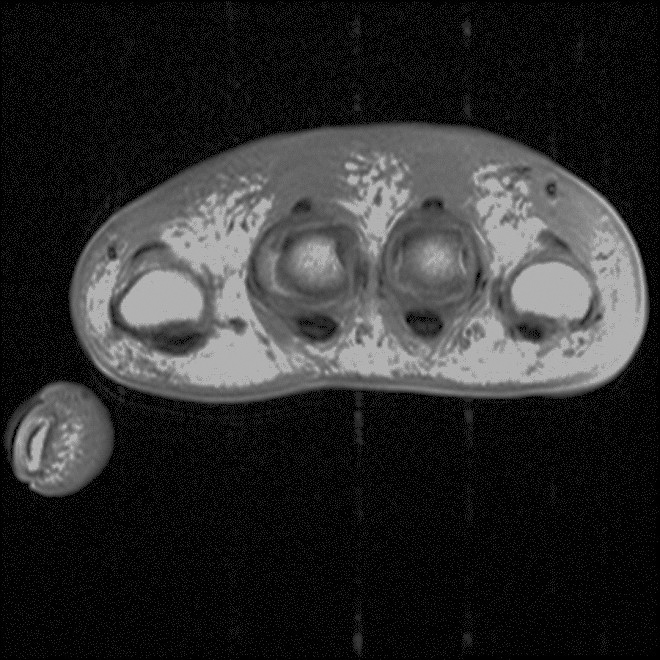

Wraparound Artifact. Axial proton-density-weighted MR image of the right knee demonstrates wraparound artifact (arrow) of the left knee, which is partially imaged (arrowhead).